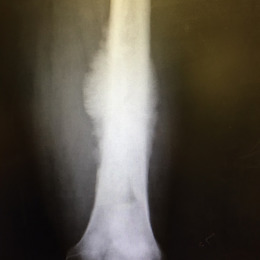

Radiographic imaging is used to help form a diagnosis. These include X-Ray, MRI, CT and Bone Scans

An example of a Conventional Osteosarcoma X-Ray is shown.

Osteosarcoma Diaphyseal